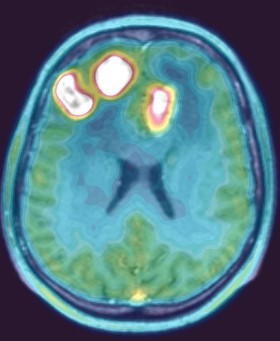

Позитронная эмиссионная томография (ПЭТ/КТ) головного мозга с 11С-метионином

Диагностика злокачественных опухолей головного мозга, выявление продолженного роста злокачественной опухоли, метастазов в головном мозге, дифференциальная диагностика рецидива опухоли и постлучевого некроза, оценка эффективности противоопухолевого лечения.

| Анапластическая астроцитома | Лимфома центральной нервной системы |